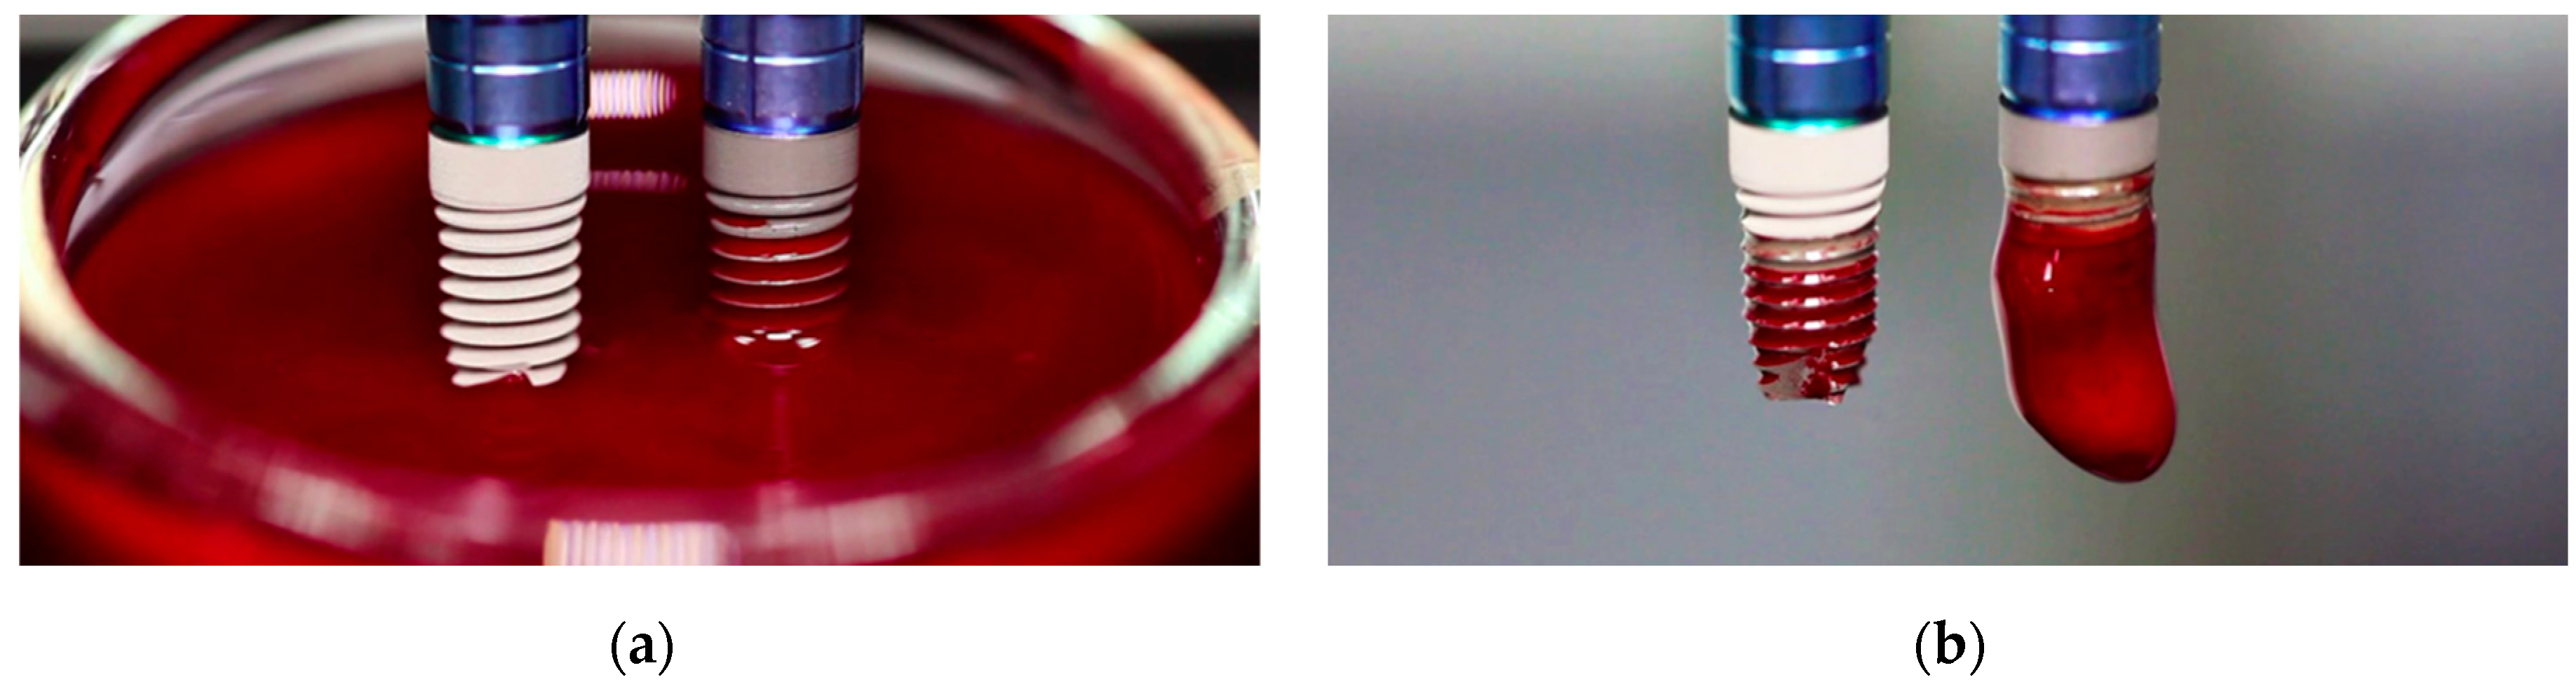

We immersed simultaneously the two implants with the two different surfaces studied in a well containing citrated blood from a healthy donor for 20 min. Figure 5 shows the two implants: an implant with a standard titanium surface (NoCa, left) and an implant modified with calcium ions (Ca, right). The implants were simultaneously put in contact with blood first and immersed then into the blood well. For the implants modified with Ca ions, blood rapidly covered the implant surface by capillarity. For the NoCa implants, though, blood progressively met the implant surface as the implant was introduced into the blood well (Figure 5a). After 20 min of incubation at room temperature, the implants were simultaneously pulled out of the blood. The implants previously modified with Ca clearly showed a clot formed around them while the implants without Ca did not (Figure 5b).

Figure 5.

Implant immersion experiments in blood. (a) First contact of the implant surfaces with blood. (b) Resulting surfaces after 20 min incubation at room temperature in the blood-containing well.